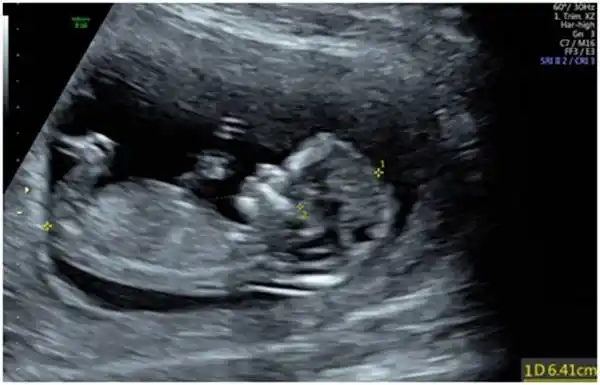

一口气教您读懂超声nt报告_胎儿_筛查_检查